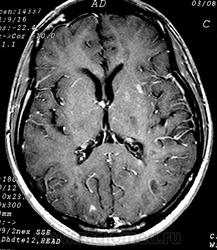

ГМ. Рассеянный склероз 3. +

Рассеянный склероз